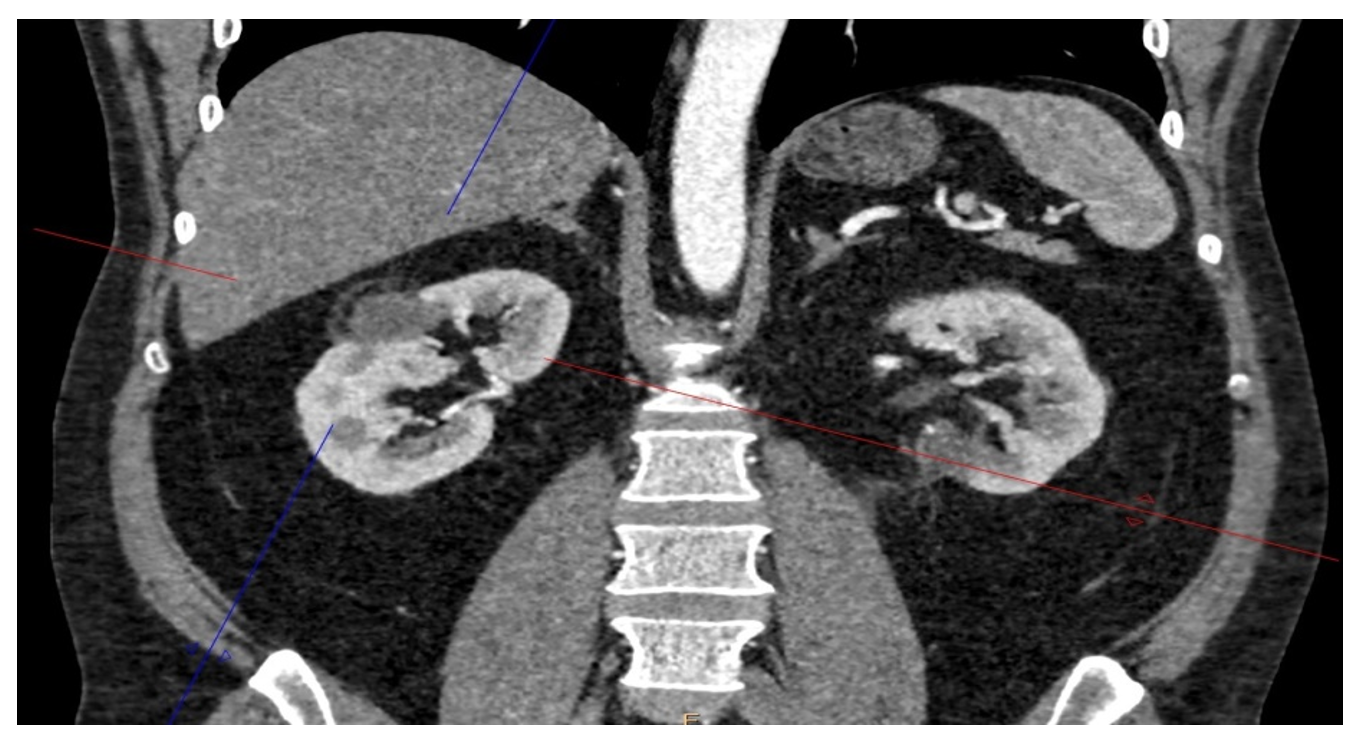

Рисунок 3 - Через 3 месяца после последнего вмешательства

Разнообразие методов хирургического лечения ПКР, (эндоскопические и полостные резекции почки и нефрэктомии, криоаблация и РЧА), позволяют проводить хирургическое лечение пациентам, различающимся по возрасту, конституциональным особенностям, соматическому состоянию. Индивидуализация подходов к хирургическому лечению ПКР позволяет добиться наибольшей результативности и обеспечить благоприятный онкологический прогноз. Данный пример клинического случая позволяет проследить эффективность комбинации эндоскопической резекции почки и криоаблации при билатеральном ПКР. Больной Л., 43 лет, в декабре 2024 обратился в ГБУ РО КДЦ «Здоровье», при КТ органов брюшной полости и почек 09.12.2024, выявлено: в среднем сегменте правой почки с умеренным экстраренальным ростом (менее 50%) — образование р-ми 25х24х27 мм, накапливающее контраст до 138 НU, RENAL 9, баллов; в нижнем сегменте левой почки с экстраренальным ростом (более 50%) образование 30х26х31 мм, накапливающее контраст до 125 HU, RENAL 6 баллов. Установлен диагноз: первично-множественный билатеральный рак почек: рак левой почки T1NoMo ST I кл. гр.2, рак правой почки T1N0M0 ST I, кл. гр.2. 12.12.2024 — эндоскопическая резекция левой почки. 13.01.2025 чрескожная криоблация опухоли правой почки с одномоментной биопсией. Послеопреационный период в обоих случая протекал без осложнений. Через 3 месяца после последнего вмешательства (криоаблации). При КТ почек с контрастированием 16.04.2025 — в правой почке — в верхней трети изоденсивная зона не накапливающая контраст р-ми 28х22х31 мм, в нижнем сегменте левой почки дефект контрастирования паренхимы 20х20х22 мм, с фиброзными изменениями. Впервые сформирована тактика лечения больного с билатеральным ПКР, основанная на комбинации высокотехнологичных хирургических методов. Применение криоаблации в данном случае позволяет снизить риски развития ОПН, инфекционных осложнений, исключить повторное анестезиологическое пособие. Данная тактика должна применяться с учётом топографических особенностей опухолей.